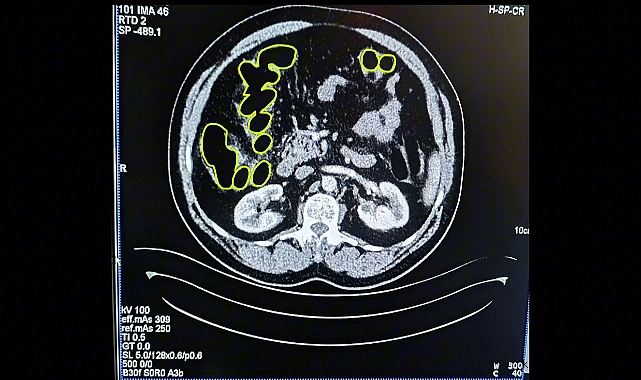

Öte yandan şahısların Kayseri Şehir Hastanesinde iç beden muayenesi yapılarak mide ve bağırsaklarında çok miktarda kapsül şeklinde uyuşturucu olduğu değerlendirilen yabancı maddeler tespit edildi. Şahıslar, vücudundaki yabancı maddelerin doğal yollardan çıkarılması için müşahade altına alındı.